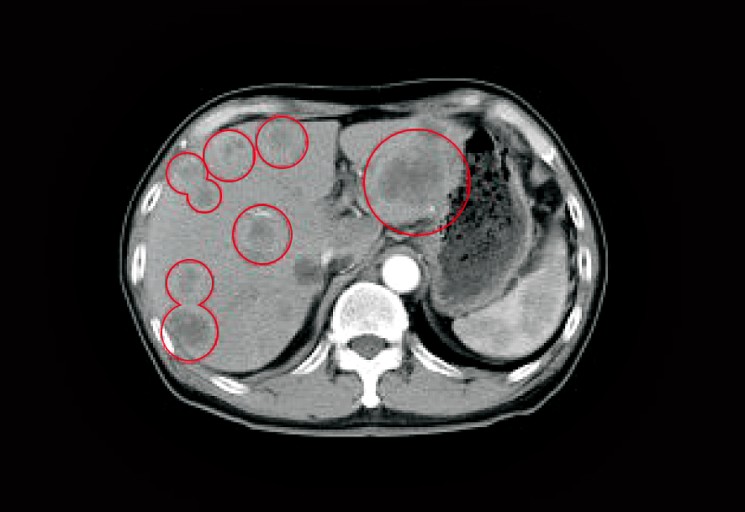

오늘은 가장 치명적인 암 중 하나로 알려진 췌장암의 초기 증상에 대해 이야기하려 합니다. 췌장암은 췌장(이자)에 발생하는 암으로, 췌장이 몸 깊숙한 곳에 위치하고 있어 초기 증상이 모호하거나 다른 소화기 질환과 비슷해 진단이 매우 어렵습니다.

췌장암은 종양의 위치나 크기에 따라 증상이 매우 다양하게 나타납니다. 초기에는 자각 증상이 거의 없어 병이 상당히 진행된 후에 발견되는 경우가 많으므로, 아래 증상들이 복합적으로 나타난다면 즉시 정밀 검사를 받아봐야 합니다. 다음은 췌장암 환자들이 흔히 겪는 10가지 주요 초기 증상입니다.

췌장암 초기증상 - 황달

- 설명: 췌장암이 췌장의 머리 부분(췌두부)에 생겨 담즙이 흐르는 총담관을 막을 때 발생합니다. 피부와 눈의 흰자위가 노랗게 변하고, 소변 색이 콜라처럼 짙어지며, 대변 색이 회색이나 하얗게 변하는 증상이 나타납니다. 황달은 비교적 초기에 발견될 수 있는 중요한 신호입니다.

- 복합적인 증상 주의: 단순 소화 불량이 아닌, 복부 통증 + 체중 감소 + 황달 + 새로운 당뇨병 등 여러 증상이 복합적으로 나타나면 즉시 병원을 찾아 정밀 검사(복부 CT, MRI, 내시경 초음파 등)를 받아야 합니다.